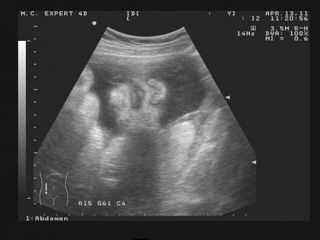

УЗИ

При нормальном течении беременности УЗИ на 36 неделе не требуется – последнее, третье плановое УЗИ уже пройдено. Однако, в отдельных случаях исследование ультразвуком может понадобиться пройти дополнительно. С его помощью врач еще раз уточнит положение ребенка в матке, исключит обвитие пуповиной и предлежание плаценты, оценит степень зрелости плаценты, ее состояние. Полученные данные помогут врачу, в том числе, и с определением метода родоразрешения,

На УЗИ в 36 неделе беременности можно заметить, что головка у малыша сейчас круглой или овальной формы. Но будьте готовы, что в первые несколько часов после родов голова новорожденного будет немного деформирована – чаще имеет заостренную форму. Это – следствие прохода крохи по родовым путям: кости черепа младенца мягкие и подвижные, в момент прохождения по родовым путям кости черепа сжимаются. Соответственно, головка новорожденного сохраняет такую форму еще некоторое время после родов, однако, затем все нормализуется.

Немного об УЗИ

Как правило, к этому сроку все плановые УЗИ уже сделаны. Но бывают случаи, когда врач рекомендует еще раз провести такое исследование. Обычно на внеплановое УЗИ имеются уважительные причины: необходимо знать точный вес ребенка, или уточнить степень зрелости плаценты, или подтвердить предродовую позицию плода, или же выяснить наличие/отсутствие обвития пуповиной.

Важность информации, полученной на контрольном УЗИ, значительно превышает потенциальную возможность вреда от ультразвука. В зависимости от результатов, определяется, какими будут роды: природными или же кесарево сечение, принимаются соответственные меры для предупреждения возможных осложнений.

На УЗИ в 36 недель родители видят малыша таким, каким он родится. Череп крохи на данный момент очень мягкий. Это не патология, а обязательное условие для успешного прохождения по родовым путям. Во время родов черепные кости сходятся в месте родничков (больших хрящевых участков) и головка малыша значительно уменьшается, приобретая яйцевидную форму. После появления на свет, кости возвращаются на свои места, а через некоторое время твердеют. В последнюю очередь зарастают роднички (обычно этот процесс завершается к году-полтора).

Важный пункт УЗИ осмотра, в этот период – предлежание плода. В идеале ребенок должен быть повернут головой к родовым путям (так называемое головное предлежание). В 4% случаев наблюдается ягодичное предлежание. В этом случае рекомендовано кесарево сечение, поскольку очень высокая вероятность родовой травмы или того, что ребенок вообще не сможет пройти родовой путь. Но, вместе с тем, нередки случаи успешных природных родов и в таком положении плода.

Ультразвуковое исследование

На 36 неделе беременности УЗИ, как правило, уже пройдено, но в некоторых случаях оно может понадобиться дополнительно. С его помощью специалист сможет определить предлежание плаценты и ее степень зрелости, положение плода в матке. Также врач с помощью исследования исключает обвитие плода пуповиной и определяет метод родоразрешения. Также необходимо уделить внимание состоянию матки и околоплодных вод.Рекомендации для мам